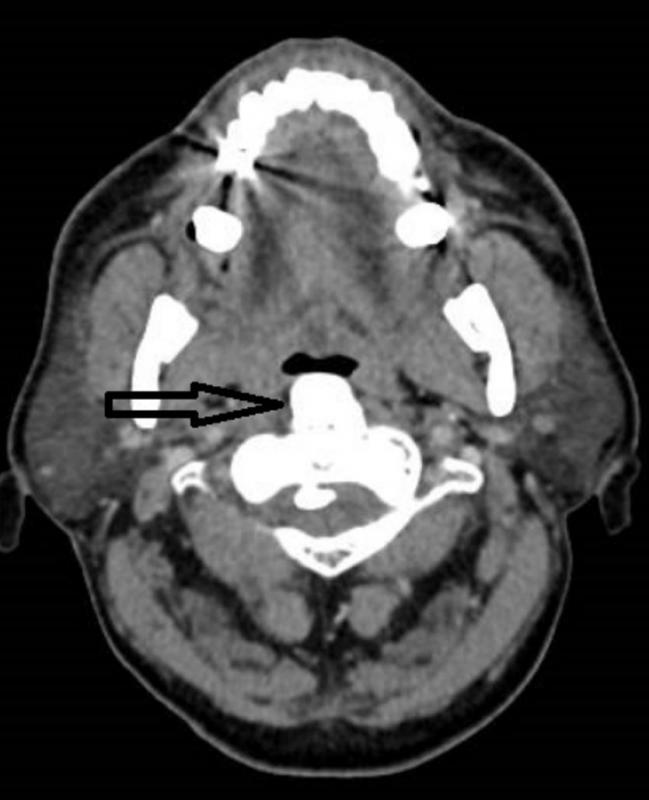

·甲状腺隐藏在舌根里:甲状腺在发育过程中未下降到颈项前的正常位置,而出现于其他部位,称为异位甲状腺。这是一种罕见的胚胎发育异常疾病。甲状腺最常隐藏的部位是舌根中线区,女性多于男性。

如果男女到了十七八岁,甲状腺还未下降到颈项前,睡觉时就容易引发窒息。治疗法是割除甲状腺,病人过后可口服甲状腺素片发挥甲状腺功能。